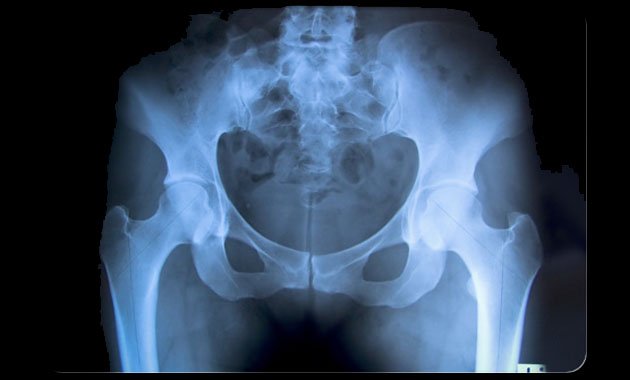

Οι γυναίκες που κάνουν φυτοφαγική διατροφή, έχουν 33% μεγαλύτερο κίνδυνο να πάθουν κάταγμα στο ισχίο (γοφό), σε σχέση με όσες τρώνε κρέας τακτικά (τουλάχιστον πέντε φορές την εβδομάδα), δείχνει μια νέα βρετανική επιστημονική έρευνα.

Οι ερευνητές του Πανεπιστημίου του Λιντς, με επικεφαλής τον Τζέιμς Γουέμπστερ, οι οποίοι έκαναν τη σχετική δημοσίευση στο ιατρικό περιοδικό «BMC Medicine», ανέλυσαν στοιχεία για 26.318 γυναίκες ηλικίας 35 έως 69 ετών, από τις οποίες οι 822 (σχεδόν το 3%) είχαν πάθει κάταγμα ισχίου στη διάρκεια περίπου 22 ετών.

Αφού ελήφθησαν υπόψη άλλοι παράγοντες όπως το κάπνισμα, βρέθηκε ότι οι φυτοφάγες γυναίκες ήταν η ομάδα με τον πιο αυξημένο κίνδυνο για το εν λόγω κάταγμα. Οι επιστήμονες τόνισαν την ανάγκη το ζήτημα να μελετηθεί περαιτέρω, ώστε να εξηγηθούν καλύτερα οι ακριβείς αιτίες που η φυτοφαγική διατροφή σχετίζεται με αυξημένο κίνδυνο κατάγματος του ισχίου.